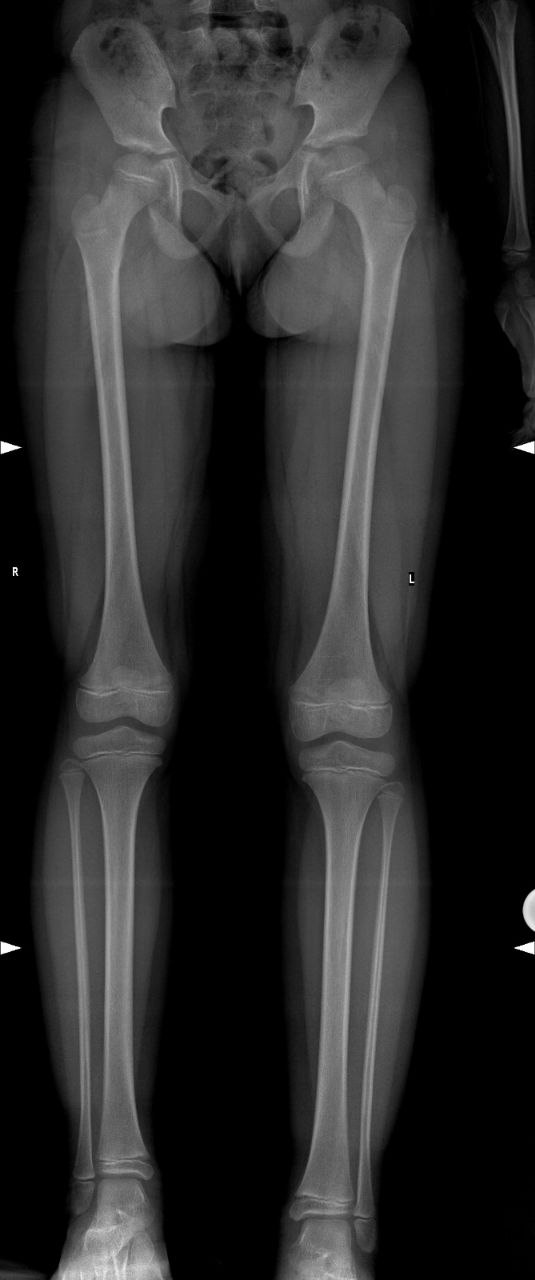

В случае подозрения на разновеликость, необходимо обратиться к детскому ортопеду для прохождения процедуры осмотра и выполнения дополнительных методов обследования. Из дополнительных методов обследования ведущее значение имеет панорамная рентгенография нижних конечностей (Full Leg).

При значительной разновеликости у детей после 12 лет методом выбора являются удлиняющие методики при помощи аппаратов внешней фиксации различных модификаций (определяется индивидуально).